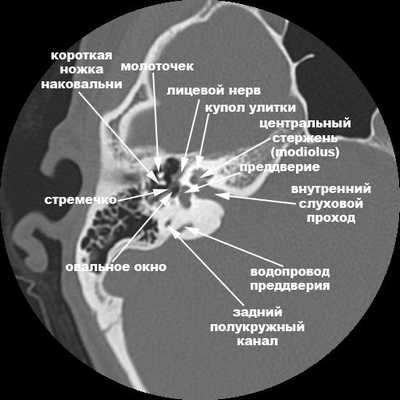

КТ левой височной кости в аксиальной проекции. Срез слева проходит выше, чем срез справа.

А, антрум; В, средняя черепная ямка; С, задняя черепная ямка;

D, поддуговая артерия; Е, верхний полукружный канал; G, внутренний слуховой проход;

Н, преддверие; I, латеральный полукружный канал; J, водопровод преддверия.

На рисунке ниже изображены аксиальные срезы КТ височных костей с основными ориентирами, направление сверху вниз. На отдельном рисунке изображен фронтальный срез. Всегда важно помнить, что КТ показывает именно костные структуры. Мембранозные образования внутреннего уха расположены внутри костных. Преддверие расположено в центре лабиринта, здесь находятся полукружный и сферический мешочки, также с преддверием соединены полукружные каналы. Лицевой, слуховой и два вестибулярных нерва проходят по внутреннему слуховому проходу от ствола мозга до внутреннего уха.